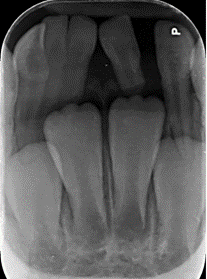

Tres meses después se realizó un control imagenológico y en la radiografía intraoral se observó inferiores permanentes seguían su proceso de erupción de forma similar, reabsorbiendo una porción de la raíz del incisivo inferior izquierdo primario, así como una porción de las raíces del central y supernumerario fusionados, sin embargo, la raíz del lateral fusionado aparentaba no reabsorberse de forma similar que las piezas fusionadas (Figura 4). Se decide mantener los dientes fusionados en boca y volver a hacer un control 4 meses después.